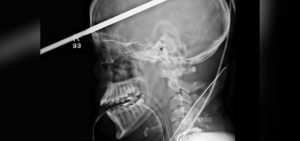

El accidente ocurrió mientras el hombre trabajaba en la construcción de una casa en Gondia, India. Repentinamente cayó a altura cercana a los dos metros de altura y lamentablemente una varilla de metal se incrustó en su cabeza.

Sorpresivamente el hombre en ningún momento perdió el conocimiento, por lo que fue trasladado a la ciudad de Nagpur.

Ahí fue ingresado a cirugía en el Hospital Neuron, el procedimiento quirúrgico duró alrededor de 90 minutos.

Médico encargado de la operación, Pramod Giri, explicó que el hombre sobrevivió ya que la varilla no dañó algún vaso sanguíneo.